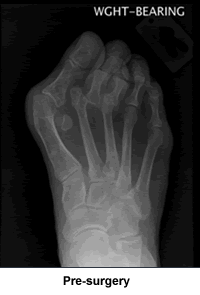

My right foot has been particularly problematic since I was six years old. It took two bunionectomies before that particular issue was finally resolved, and all was tolerably well until a year ago. The right foot once again reared its ugly (and I do mean ugly) head and began giving me all kinds of pain and discomfort. The orthopedic surgeon who had performed my second bunionectomy ordered a set of radiographs. When he saw what was happening he sent me to New England Baptist to see Dr. Leavitt. Dr. Leavitt was very impressed (from a medical science standpoint) and sympathetic (from a humanistic standpoint) as we looked at the x-rays and discussed what was happening to the bones. While not downplaying the inconvenience that I would go through, he confidently explained what he would be doing in surgery and how he had no doubt the problems would be resolved to my satisfaction. He came to see me right before and after the surgery, kind, upbeat, and optimistic. This was very reassuring, both to my husband and me.